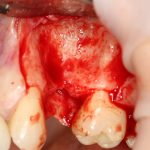

Забор костного фрагмента проводится с наружной косой линии с помощью ультразвукового пьезохирургического инструмента. Ничего сверхнового и супернеобычного тут нет, совершенно стандартная методика. С той лишь разницей, что молоток для этого используют только фашисты и только в гестапо использовать не нужно, всё делается усилием и ловкостью рук.

Нюансы начинаются с обработки принимающего ложа. Да-да, уважаемые друзья, одна из причин некроза блоков, их чрезмерной атрофии и прочих проблем — в отсутствии обработки принимающего ложа. Некоторые делают дырки, но правильнее и эффективнее поступить так:

то есть, просто снять слой кортикальной пластинки с участка, к которому будет фиксироваться костный блок. Почему? Читайте здесь>>.

Вторая особенность — мы не адаптируем и не обрабатываем костный блок invitro, а фиксируем его так, как есть:

после чего обрабатываем — доводим до окончательной формы альвеолярного гребня: